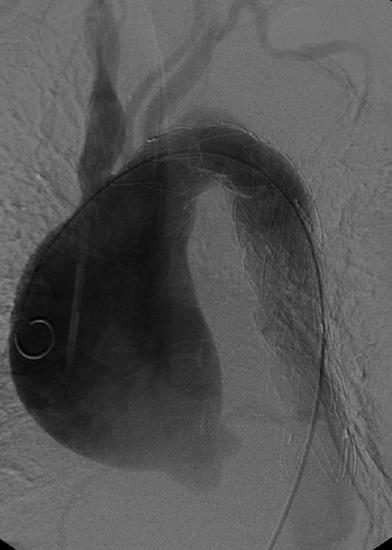

Die Aortenchirurgie behandelt überwiegend Aneurysmen (Erweiterungen der Hauptschlagader) sowie Dissektionen (Einrisse in die Wand der Hauptschlagader) (Abb. 1.). Durch Schädigung der elastischen Anteile einer Gefäßschicht (Media) kommt es zur chronischen Ausweitung und Schwächung der Schlagader. Diese Ausweitung kann unterschiedliche Formen (sackartig, birnenförmig etc., Abb.1.) haben. Ab einem gewissen Durchmesser (je nach zugrunde liegender Erkrankung bei ca. ±5cm) sollte eine operative Sanierung durchgeführt werden, da ansonsten die Ruptur des Gefäßes droht. Durch die Ausdehnung des Gefäßes beim Aneurysma kommt es zu einer Ausdünnung der Aortenwand und zum überproportionalen Anwachsen der Wandspannung, somit zur massiven Schwächung der Gefäßwand. Bei Blutdruckanstieg zerreißt die Aorta, eine in den meisten Fällen tödliche Komplikation.

Abb. 1. Sackartige Ausweitung der aufsteigenden Hauptschlagader (Aorta-Ascendens-Aneurysma, Angiographie)